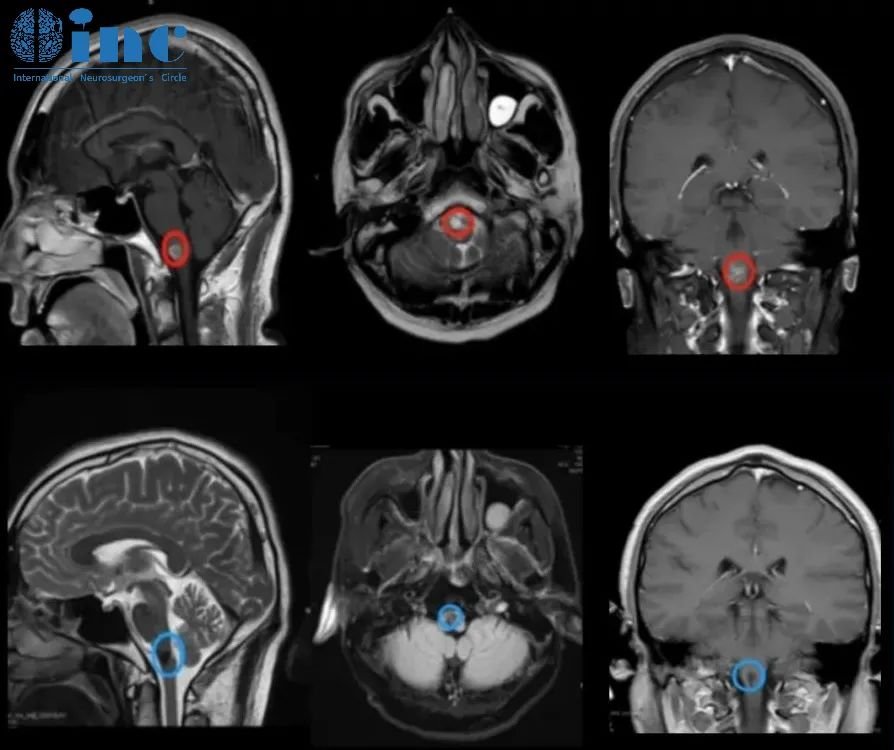

50岁女性-延髓海绵状血管瘤

28岁女性-脑干延髓海绵状血管瘤

19岁男孩-延髓海绵状血管瘤

32岁男性-延髓海绵状血管瘤

30岁女性-延髓-颈髓海绵状血管瘤